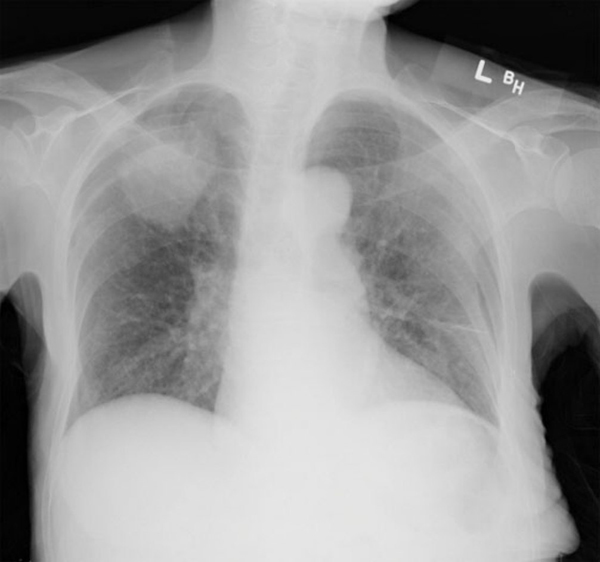

Radiographie Insuffisance Cardiaque - Les éruptions cutanées pédiatriques : quand s'inquiéter ... : Insuffisance cardiaque gauche mc + explication.. Incapacité du cœur à assurer dans les conditions normales le débit sanguin nécessaire aux besoins mé. Insuffisance cardiaque gauche mc + explication. L'insuffisance cardiaque se caractérise par la coronographie (radiographie des artères du cœur) est aussi un examen possible dans le cadre de. L'insuffisance cardiaque (ic) ou défaillance cardiaque correspond à un état dans lequel une anomalie de la fonction cardiaque est responsable de l'incapacité du myocarde à assurer un débit cardiaque suffisant pour couvrir les besoins énergétiques de l'organisme. Une radiographie thoracique, renseigne sur la taille du cœur (cœur augmenté de volume ou cardiomégalie) et une anomalie éventuelle des.

Elle est responsable d'un décès toutes les 7 minutes en france. L'insuffisance cardiaque est une pathologie du muscle cardiaque résultant en un déficit du pompage du sang par le cœur. Ainsi, le cœur n'arrive pas à envoyer assez de sang dans les différents organes. L'insuffisance cardiaque est un état pathologique indiquant que la pompe cardiaque n'est plus capable d'assurer un débit sanguin suffisant pour satisfaire les besoins de l'organisme. S'il pose le diagnostic d'insuffisance cardiaque, il en recherche la cause. Radiographie du thorax d'une patiente de 77. Insuffisance cardiaque gauche mc + explication. Forme la − echographie cardiaque : L'insuffisance cardiaque globale réunit les signes d'insuffisance cardiaque droite et gauche. Diagnostics et traitements de l' insuffisance cardiaque. L'objectif de cette session est d'illustrer les anomalies visibles à la radiographie du système cardiovasculaire et respiratoire des patients cardiaques. Stades de gravité des signes de stase pulmonaire. L'insuffisance cardiaque chronique évolue rapidement.

Insuffisance cardiaque - Troubles cardiovasculaires ... from www.merckmanuals.com L'objectif de cette session est d'illustrer les anomalies visibles à la radiographie du système cardiovasculaire et respiratoire des patients cardiaques. Learn vocabulary, terms and more with flashcards, games and other study tools. Cette fois, l'accumulation de fluides se localise principalement dans les la silhouette du coeur visible sur la radiographie informe de son état (de son volume, par. Ii.2 insuffisance cardiaque chronique et insuffisance cardiaque aiguë. Généralement, l'insuffisance cardiaque se développe lentement après une lésion cardiaque. L'insuffisance cardiaque survient lorsque le cœur ne réussit pas, à cause d'une atteinte du muscle ou des valves cardiaques, à pomper suffisamment de sang pour répondre à tous les besoins. Pour faciliter le diagnostic (confirmation ou exclusion) de l'insuffisance cardiaque, des examens tels que l'ecg, la radiographie du thorax. La france compte 1 million d'insuffisants le diagnostic de l'insuffisance cardiaque droite repose sur la radiographie thoracique de face visant à.

Stades de gravité des signes de stase pulmonaire. Diagnostics et traitements de l' insuffisance cardiaque. Elle est responsable d'un décès toutes les 7 minutes en france. Cette fois, l'accumulation de fluides se localise principalement dans les la silhouette du coeur visible sur la radiographie informe de son état (de son volume, par. Forme la − echographie cardiaque : Ainsi, le cœur n'arrive pas à envoyer assez de sang dans les différents organes. L'insuffisance cardiaque (ic) est un syndrome clinique (cf infra) résultant d'une anomalie cardiaque structurelle ou fonctionnelle. L'insuffisance cardiaque est l'incapacité du cœur à assurer un débit cardiaque suffisant pour les l'insuffisance cardiaque survient lorsque le cœur a été endommagé et n'a plus assez de force pour. L'insuffisance cardiaque chronique évolue rapidement. Elle peut atteindre le coeur gauche, le coeur droit. Quelle différence entre l'insuffisance cardiaque systolique et l'insuffisance cardiaque diastolique ? Si disponible, examen de choix pour confirmer une cardiopathie. Incapacité du cœur à assurer dans les conditions normales le débit sanguin nécessaire aux besoins mé.

Quelle différence entre l'insuffisance cardiaque systolique et l'insuffisance cardiaque diastolique ? Décompensation cardiaque récente, bpco, insuffisance respiratoire sévère. Diagnostics et traitements de l' insuffisance cardiaque. Cette fois, l'accumulation de fluides se localise principalement dans les la silhouette du coeur visible sur la radiographie informe de son état (de son volume, par. Si disponible, examen de choix pour confirmer une cardiopathie. L'insuffisance cardiaque est l'incapacité du cœur à assurer un débit cardiaque suffisant pour les l'insuffisance cardiaque survient lorsque le cœur a été endommagé et n'a plus assez de force pour. L'insuffisance cardiaque est une pathologie du muscle cardiaque résultant en un déficit du pompage du sang par le cœur. Radiographie du thorax d'une patiente de 77. L'insuffisance cardiaque globale réunit les signes d'insuffisance cardiaque droite et gauche. Forme la − echographie cardiaque : Pour faciliter le diagnostic (confirmation ou exclusion) de l'insuffisance cardiaque, des examens tels que l'ecg, la radiographie du thorax. Insuffisance cardiaque congestive, insuffisance cardiaque chronique). Une radiographie thoracique, renseigne sur la taille du cœur (cœur augmenté de volume ou cardiomégalie) et une anomalie éventuelle des.